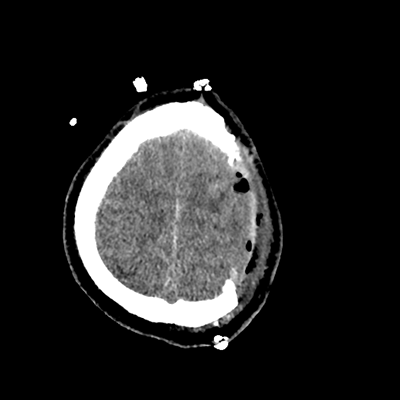

On day 5 of admission, he begins having intracranial hypertension again, spiking up to 40mmHg. You bolus with propofol and fentanyl, to no avail. You then push 30mL of 23.4% NaCl, which provides some brief improvement, allowing you to quickly get a non-contrast head CT. Unfortunately, he's now back up to 36mmHg. You review his labs, and note the following: Na 150, K 3.8, Cl 119, HCO3 18, BUN 21, Cr 0.85, glucose 136, sOsm 320.

NCHCT

NCHCT 3/20 3/20

NCHCT 4/20 4/20